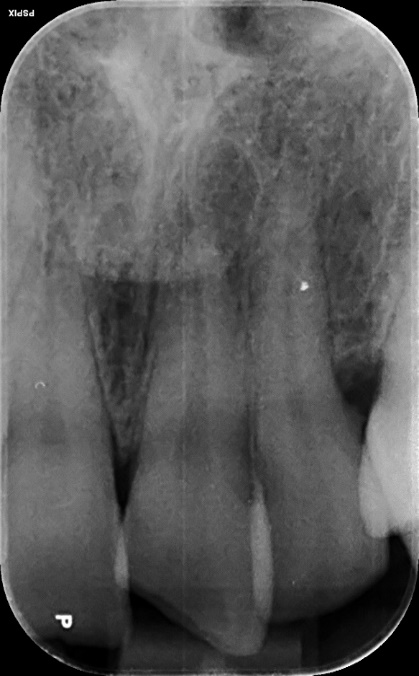

Upper Incisor trauma case primary root canal treatment and rebuild